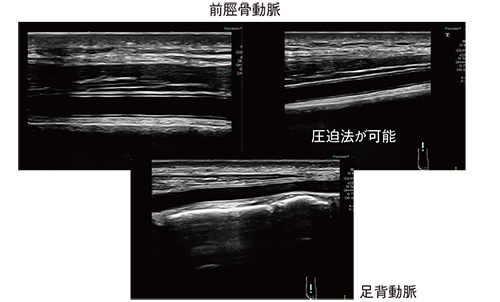

22MHzホッケー型リニアプローブで特筆すべきは,例えば,前脛骨動脈や足背動脈においてもIMTを明瞭に描出可能なほか,プローブの形状を生かして圧迫法を用いることも可能なことである(図11)。画質はPLI-705BXと遜色なく,IMTの描出においては,むしろ22MHzホッケー型リニアプローブの方が良好である。

図11 22MHzホッケー型リニアプローブによる前脛骨動脈および足背動脈のIMTの描出